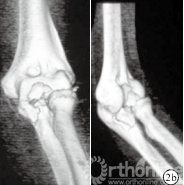

图 2 患者,男,23 岁,左侧尺骨冠状突骨折(Ⅱ型)

b.术前肘关节 CT 三维重建